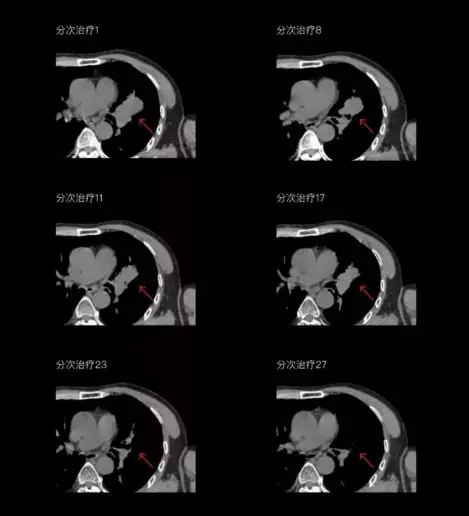

一體化CT-linac讓自適應(yīng)放療ART概念變?yōu)楝F(xiàn)實?;颊呷煶虪顟B(tài)監(jiān)控,適時在線調(diào)整治療計劃,精準控制治療劑量,為患者動態(tài)定制個體化治療方案。uAI賦能智能勾畫和自動計劃,秒級勾勒靶區(qū)和危及器官,大幅縮短自適應(yīng)放療時間。

在線自適應(yīng)放療流程示意圖

聯(lián)影CT-linac全程監(jiān)測治療過程病灶的變化,及時調(diào)整和優(yōu)化治療方案